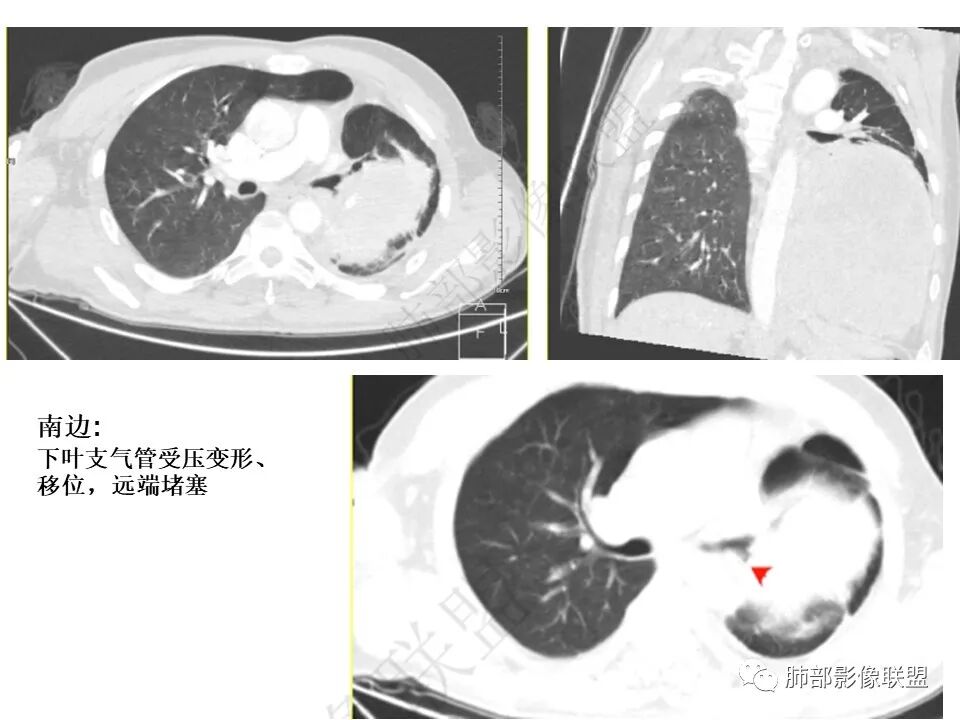

男,50岁,双下肢水肿10余天,发热3天。NSE、细胞角蛋白19片段增高。胸部CT:肺气肿背景,左下叶巨大肿块,边缘膨隆明显,与周围界限清楚,累及左肺门、左上叶,上叶支气管受压狭窄,下叶支气管截断,不均匀强化,湖泊样坏死,肿块边缘粗大点状钙化,肿块内血管影迂曲、模糊,蛇纹?考虑恶性,鳞癌?肉瘤样Ca?鉴别SFT。

南边:

还是支持脏层胸膜来源SFT首选,其次肺内肉瘤

因为:

1局部胸膜起源,所以与胸膜分界不清

2、肺内病变,局部胸膜侵犯

如果胸膜侵犯,局限在这里,而且支气管侵犯不是很明显,似乎不合理

内部坏死都可以,钙化,SFT几率高一些

2.左肺巨大块影,上部边界较清楚,占据胸腔大部,对于左肺,“占据”及“推移”兼而有之,左肺上叶支气管推移狭窄,下叶支气管截断。下肺动脉穿行!